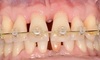

Cas 5b

L’atteinte osseuse et la quantité de tartre face interne des dents sont telles que la pose d’une attelle face interne des incisives est impossible.

Cas 5c

L’attelle de type orthodontique est collée face externe des dents. L’attelle maintient les dents et permet au praticien d’éliminer le tartre grâce à un surfaçage sans laisser les dents « flotter » à la fin du soin. Après le surfaçage, les cicatrisations osseuse et gingivale seront majorées grâce à l’attelle de soutien. Cette attelle est provisoire et une attelle d’usage en résine renforcée à la fibre de verre sera posée face interne des dents à la fin du traitement parodontal par un cabinet spécialisé de Paris.